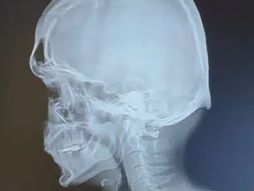

Godinama su govorili da je išijas, a onda su lekari zanemeli pred snimkom: "Veličine grejpfruta je..."

10 GODINA trpela bol u leđima, niko joj nije verovao: Ovo se krilo u njenoj KIČMI, završilla je u kolicima

Nadica je dva puta imala prelome kičme nakon porođaja, ali njeni bolovi su ignorisani: Priča hrabre Nišlijke